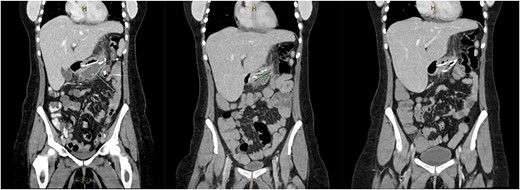

A 31-year-old female, 6 weeks post laparoscopic sleeve gastrectomy presented to the emergency department with epigastric pain and vomiting. Initial bloods showed raised inflammatory markers with a white cell count of 15.5 × 109/L and C-reactive protein of 342 mg/L. Initial CT on presentation showed the presence of a 14 × 7 × 5 cm3 gas and fluid filled collection adjacent to the staple line (Fig. 1). The patient was resuscitated with adequate fluids and kept nil by mouth. Prompt broad spectrum antibiotics were commenced. An 8Fr firm nasobiliary tube was placed directly into the collection via the defect near the GOJ under endoscopic guidance and placed on suction. During the same endoscopic procedure, a feeding nasojejunal tube was placed to ensure adequate nutrition. Given the extent of the collection, sequential advancement of the nasobiliary tube over the course of 23 days was required to ensure adequate drainage. The collection was monitored with repeat CT scans until resolution (Fig. 2). The GOJ defect was then endoscopically closed with an over the scope clip on Day 23 post presentation. The patient was discharged home post a repeat CT showing complete resolution of the collection and no oral contrast medium extending into the site of the previous collection.

Coronal CT image showing staple line collection at time of presentation. The image shows a 14 × 7 × 5 cm3 collection adjacent to the sleeve gastrectomy staple line.